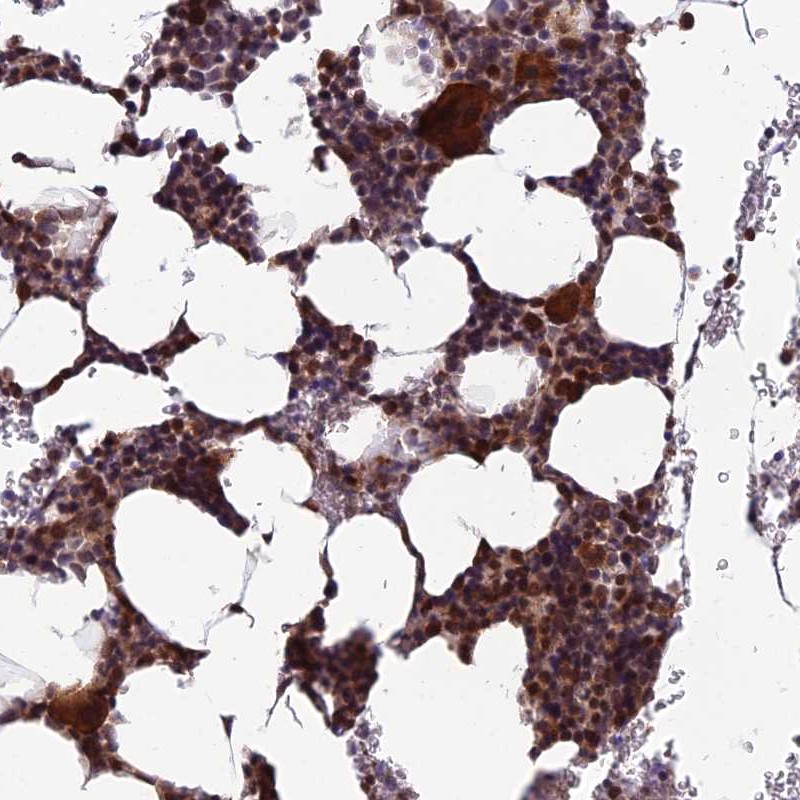

Immunohistochemical staining of human bone marrow shows strong cytoplasmic and nuclear positivity in hematopoietic cells.